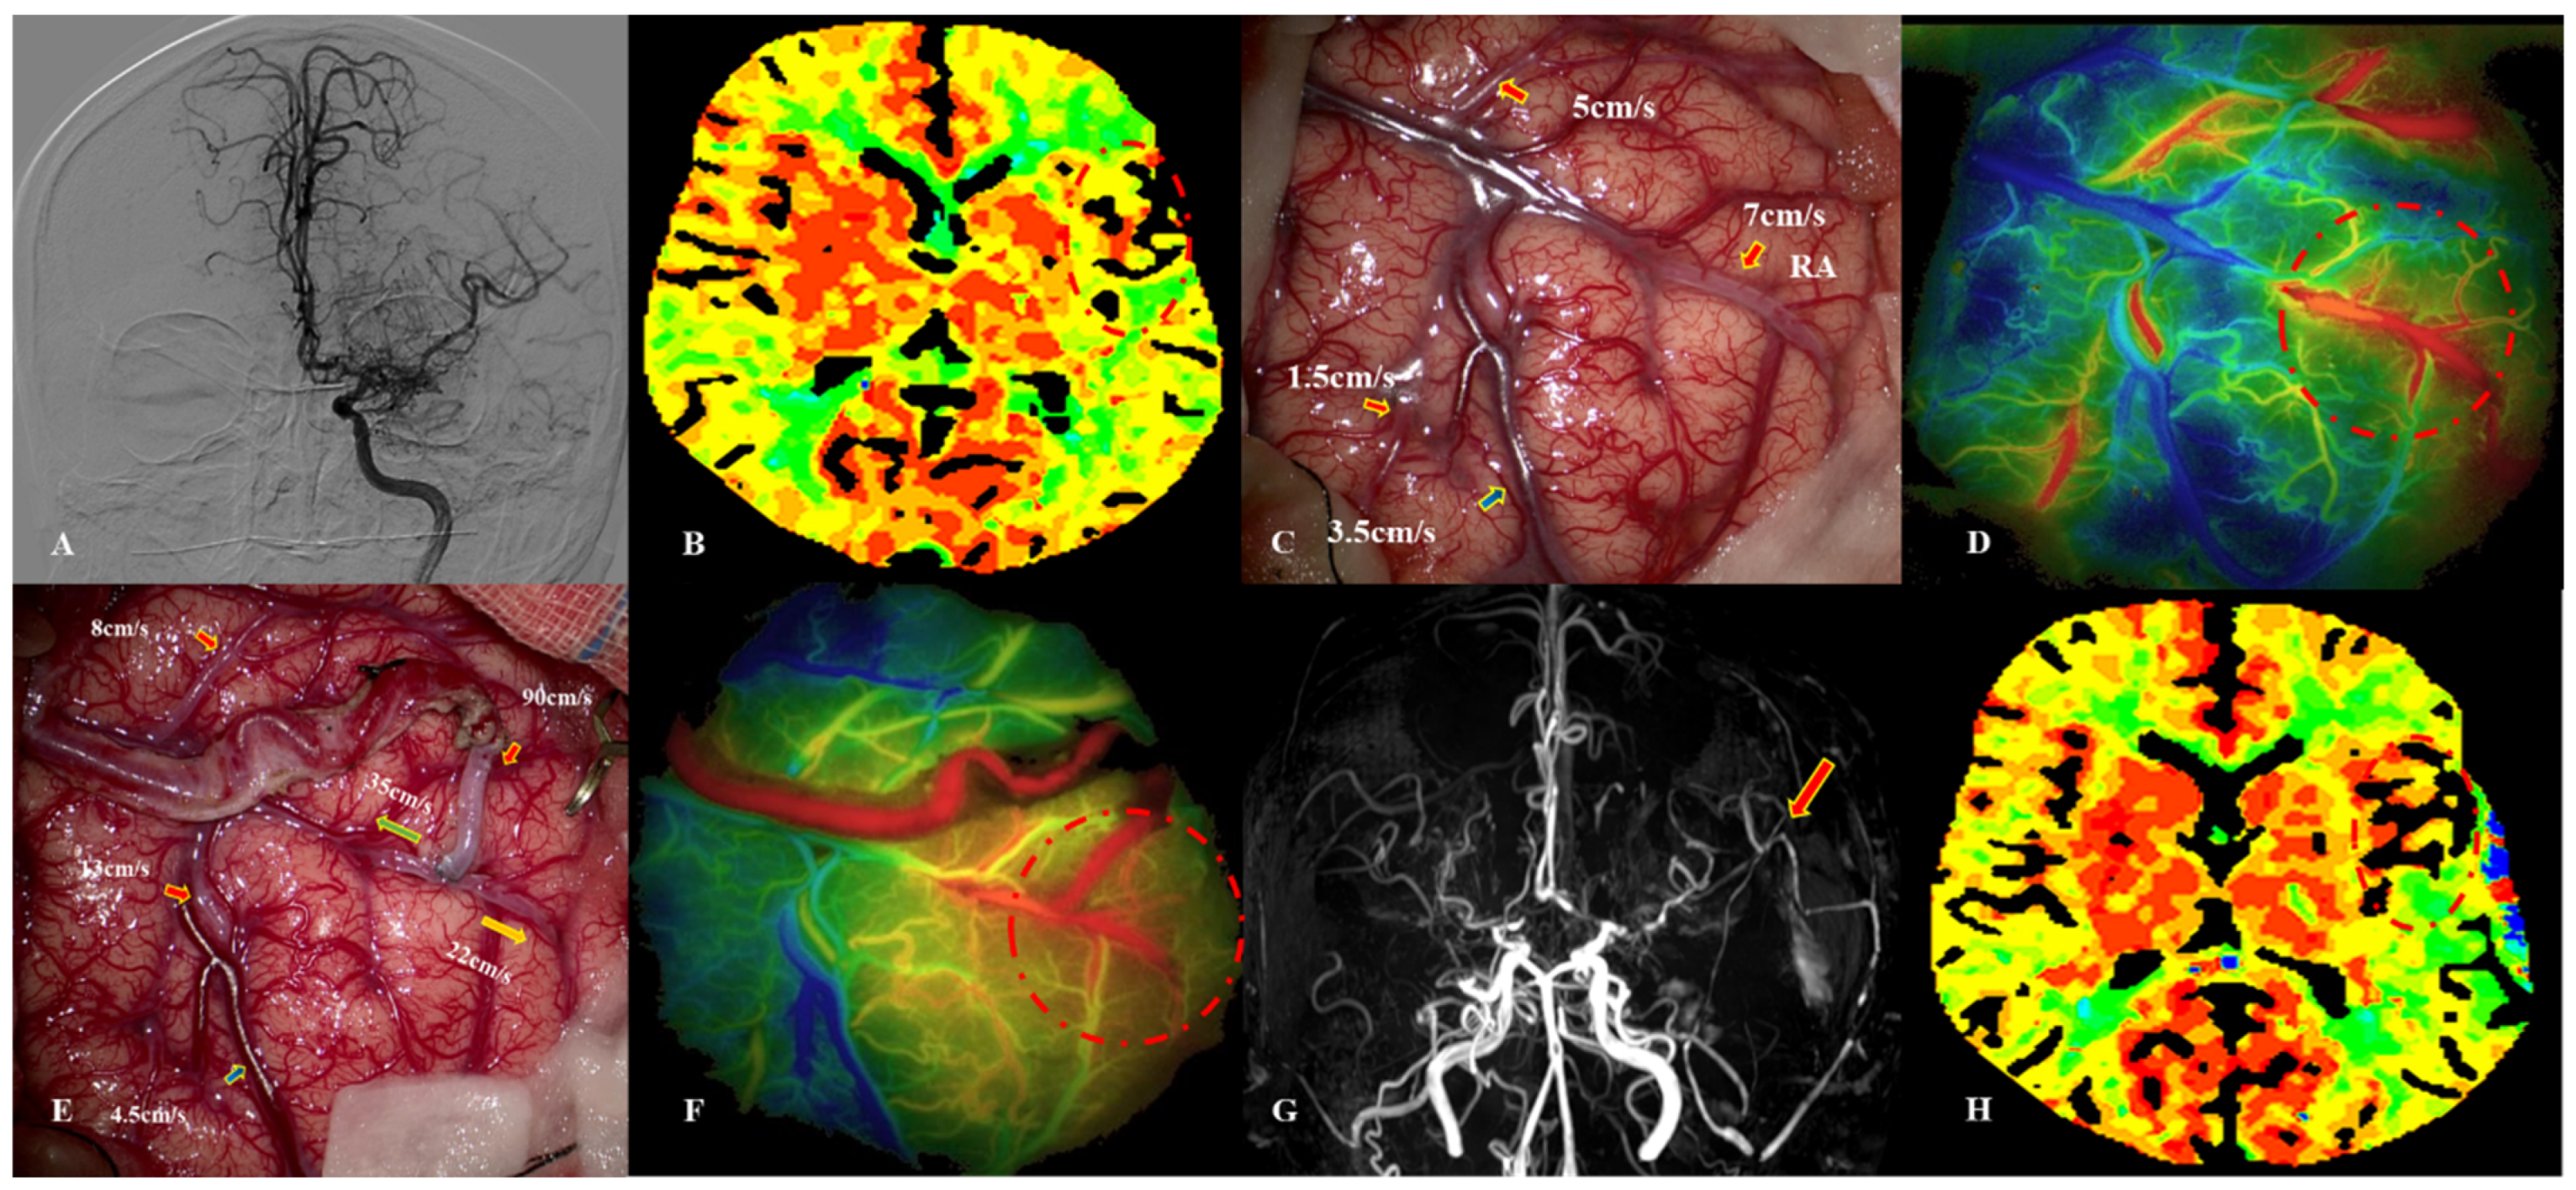

5.2. MDU Findings in Cases with CHS